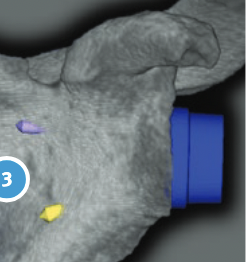

Patient specific instrumentation

Zimmer PSI Trabecular metal rTSA

Zimmer Signature One Surgical technique PDF

Metaglene / baseplate fixation

Screws as long as possible

- inferior screw - long into scapular pillar

- superior screw - aim for coracoid

- anterior / posterior screws - convergent / divergent